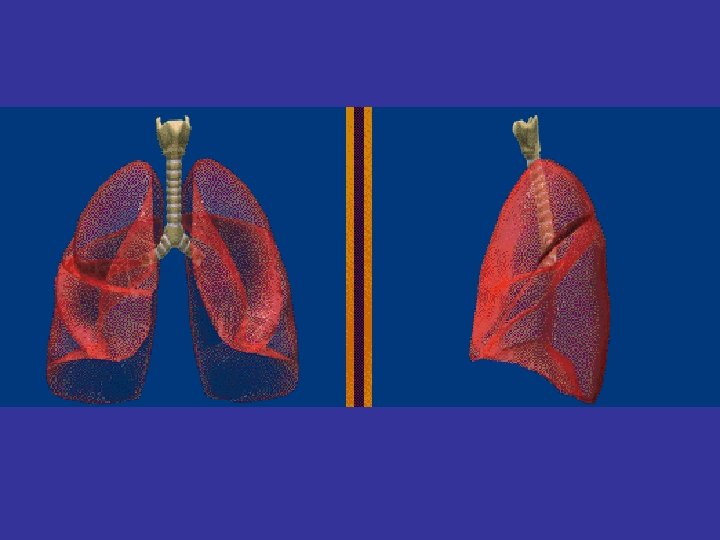

Lobes and Fissures